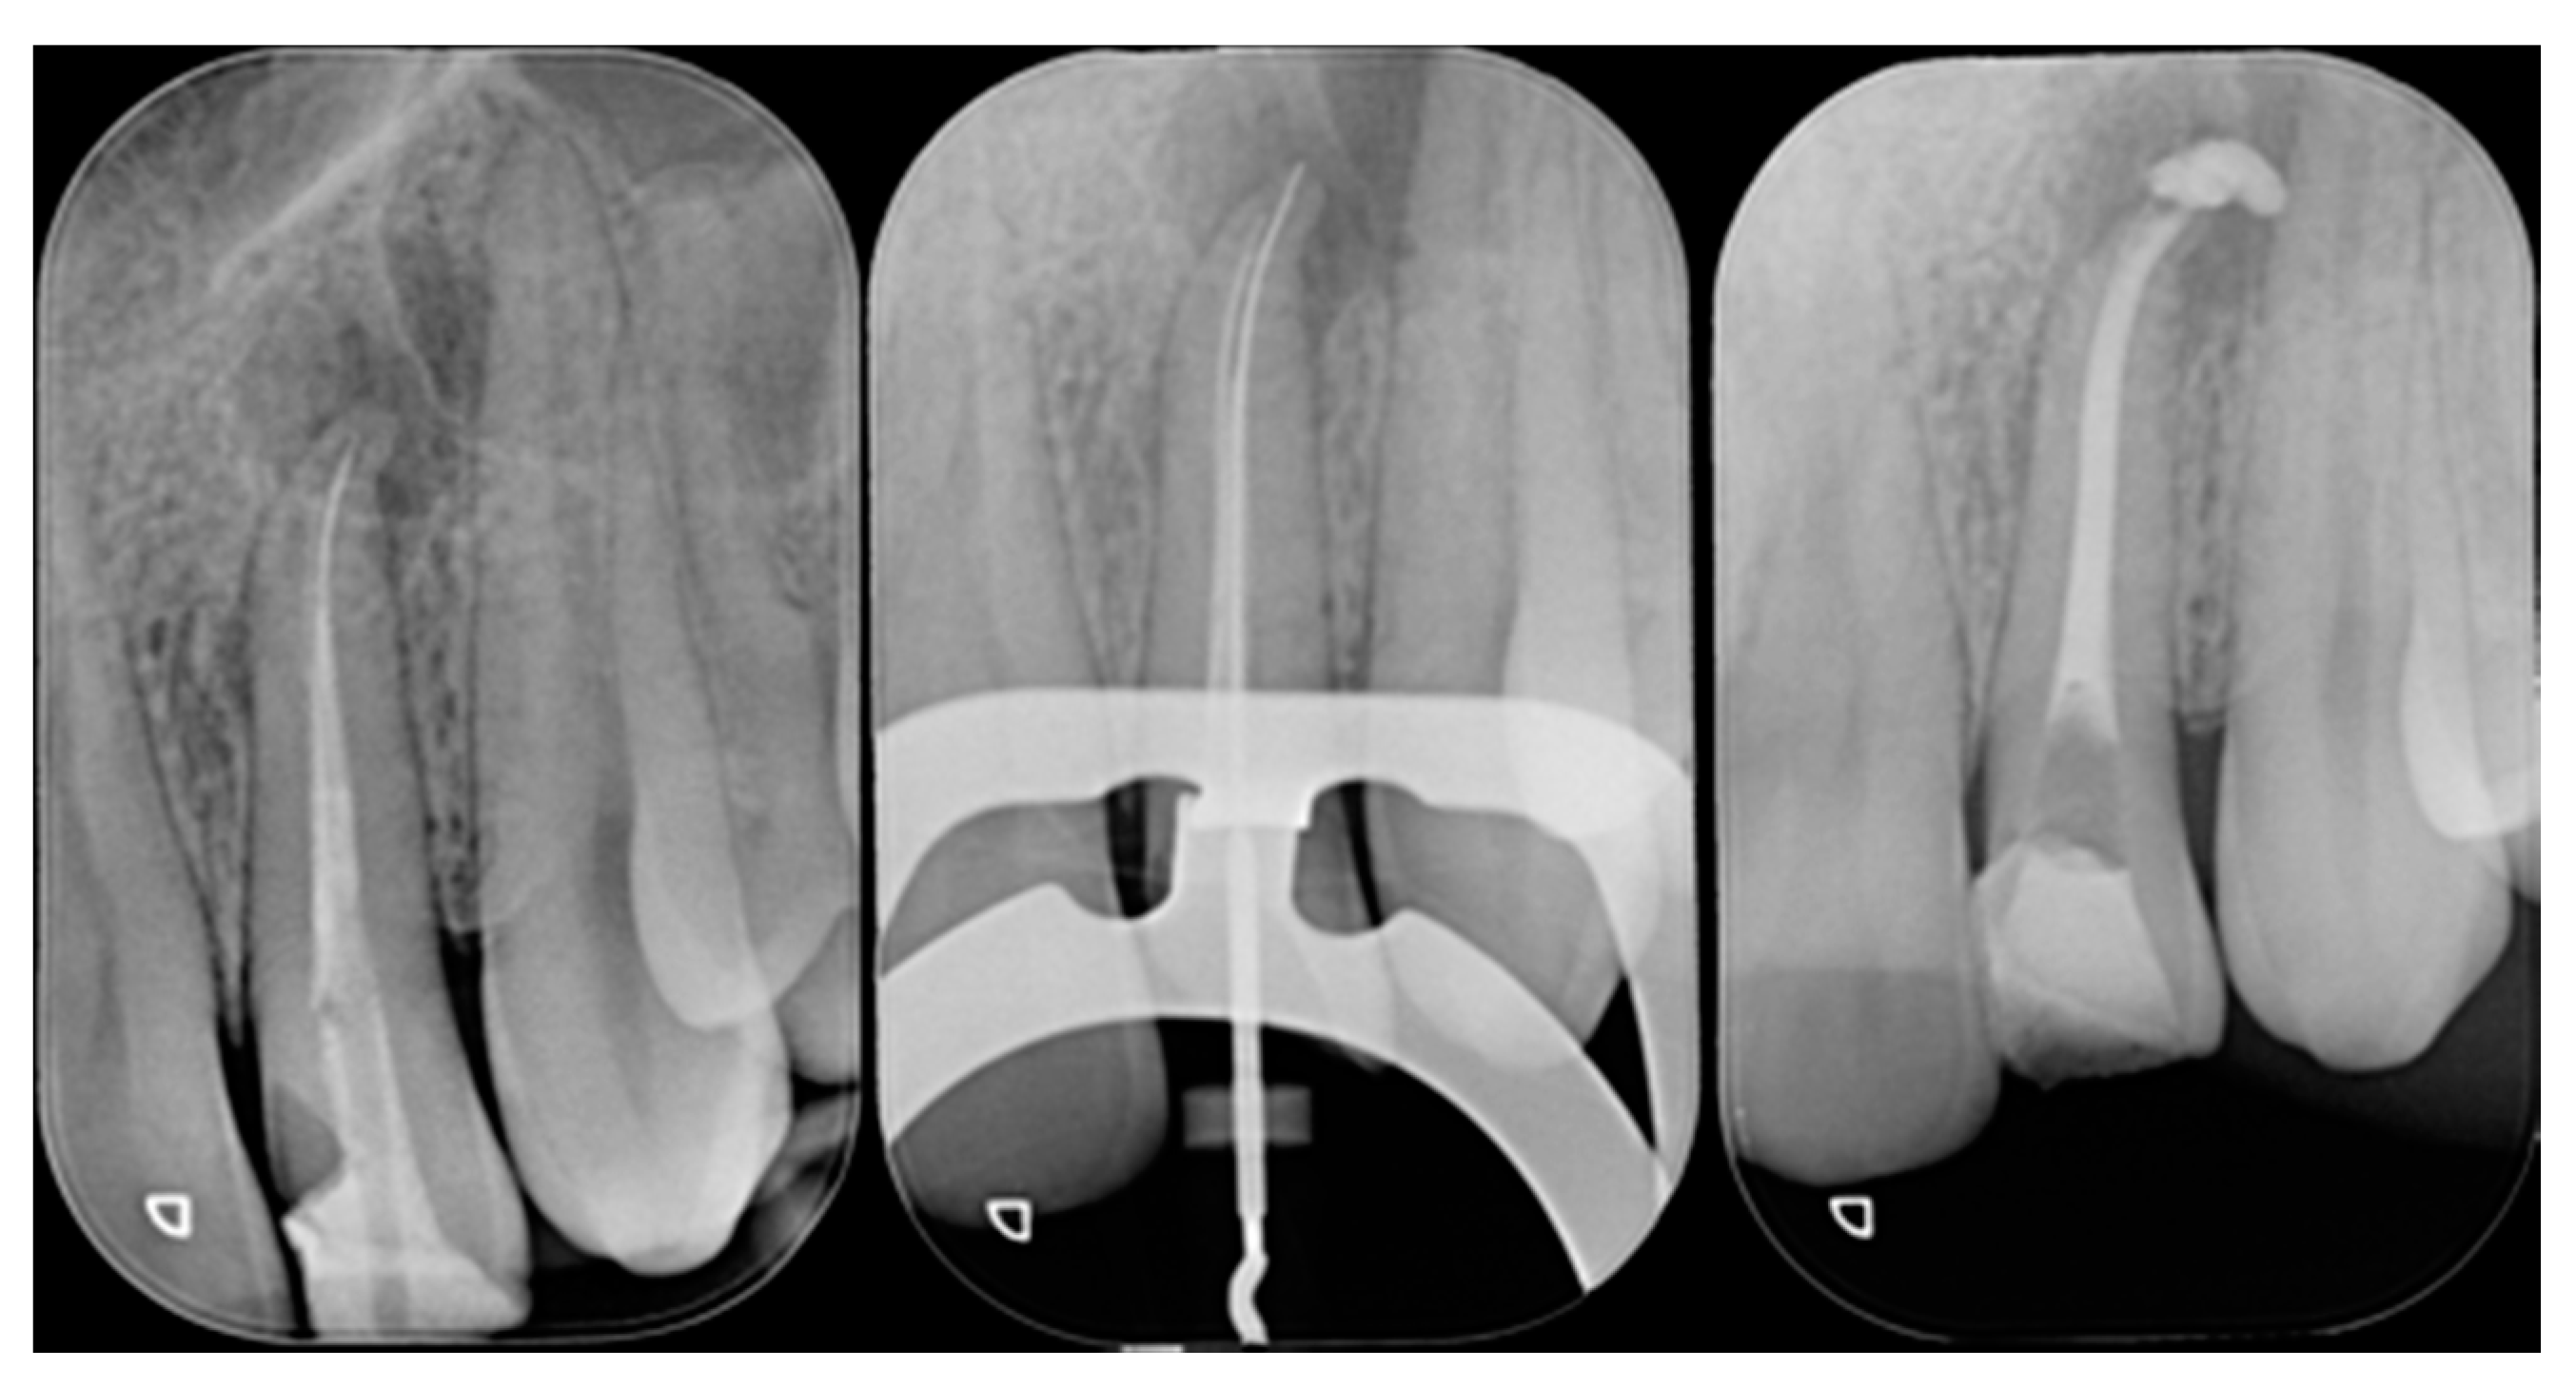

Figure 21.

Initial x-ray, during and after endodontic retreatment. Reprinted from Restauri diretti nei settori anteriori, G. Paolone, S. Scolavino, © 2021, with permission from Quintessence Publishing Italy.